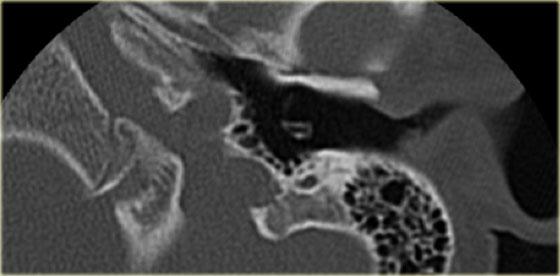

Bên trái là hình ảnh của một bé trai 16 tuổi, được khám tiền phẫu vì cholesteatoma tai phải.

Là một phát hiện tình cờ, có hình ảnh ống bán khuyên ngoài phình to (mũi tên vàng) và vắng mặt ống bán khuyên trên (mũi tên xanh dương).

Tại vị trí dự kiến của ống bán khuyên trên chỉ quan sát thấy một gờ nhỏ.

Ống bán khuyên sau bình thường.